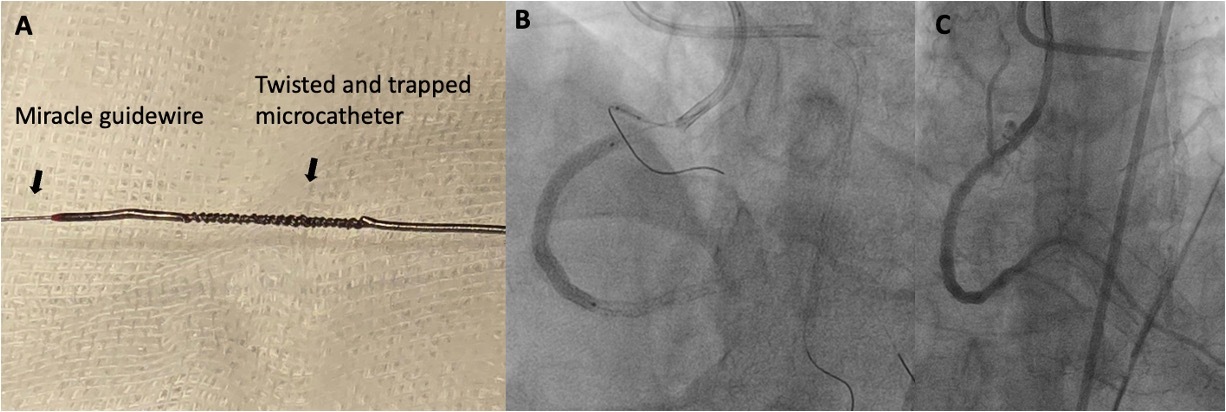

We first advanced a 0.75 Amplatz left catheter through the femoral sheaths. Next, we advanced a Mamba Flex microcatheter (Boston Scientific) and performed antegrade wire escalation with Miracle 3 and 6 guidewires (Asahi) (Figure 1B). We managed to cross the proximal and distal cap and advanced the microcatheter to perform the guidewire exchange (Figure 1C, Video 2). However, due to over-torquing, the microcatheter became twisted on the guidewire (Figure 2A, Video 3). As a result, when trying to remove the guidewire or the microcatheter, we encountered resistance. Therefore, we could not remove either the guidewire or the balloon in isolation.

As a rescue maneuver, we advanced a second Miracle 6 guidewire and a Mamba Flex microcatheter in parallel (Figures 2B and C, Video 4), using the guidewire and the trapped microcatheter as a reference. In the same manner, we managed to cross the lesion and bring the guidewire to the distal segment of the posterior descending artery. With the second guidewire in the distal location, we decided to remove the guidewire and the trapped microcatheter (Figure 3A) using the Miracle guidewire as a partial workhorse.